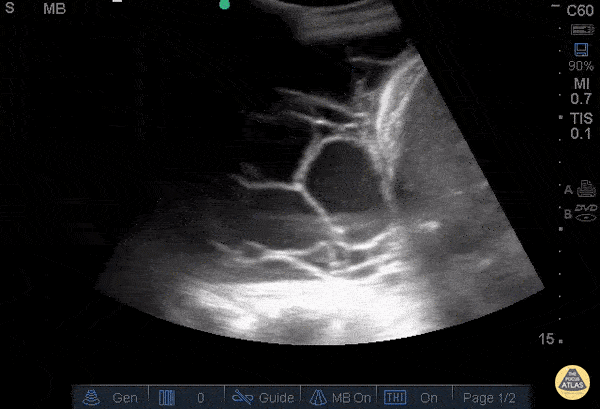

Elderly male coming in with generalized weakness, shortness of breath and cough, who had recently been hospitalized for pneumonia. On arrival he was tachypneic and satting in the high 80s on room air. POCUS in the RUQ and right lung base. Pleura and loculations are visualized along with spine sign which indicates a plueral effusion. Sonographic evidence of septations in the presence of empyema predicts the need for intrapleural fibrinolytic therapy, longer duration of drainage, or possible surgical intervention. Dr. Gina Pan - Kings County Emergency Medicine